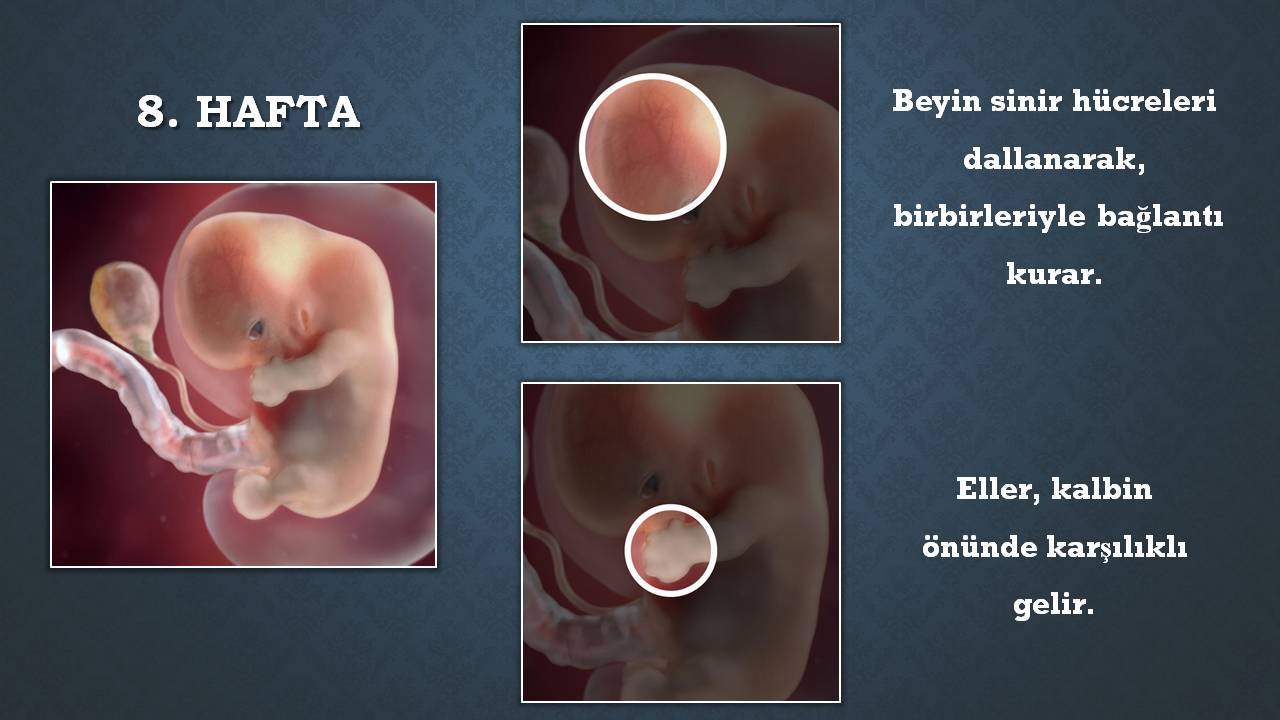

Gebelikte 8.haftada bebek boyu yaklaşık olarak 1.4 ile 2 cm civarına denk gelir. Vücudunun uzantıları gelişirken istemsiz hareketlenmeler de başlar. Bebeğin karnının içinde hareket ediyor ancak sen henüz hissedemiyorsun. Gebelikte 8.haftada bebek boyu yaklaşık olarak 1.4 ile 2 cm civarına denk gelir. Kesin olay şey ise 8 hafta sonrasında yani 9 haftalık gebelikte bebeğin kalp atışlarını izleme olasılığının epey yüksek oluşudur. 8 haftalik bebek hareket eder mi̇? 18 haftalık gebeyim dün bebeğim 2 defa hareket etti ama bugun hiç etmedi genelde yemekten sonra. Bu hafta aralığında anne bebeğinin hıçkırıklarını kolayca hissedebilir. 14 haftalık bebek hareket eder ama siz hissedemezsiniz malesef.

Bebeğin yeri geniş olduğu için anne bebeğinin taklalarını, dönmelerini çok rahat hissedebilir. 8 haftalık gebelikte bebek hareket eder mi. Bu hafta aralığında anne bebeğinin hıçkırıklarını kolayca hissedebilir. Haftadan sonra her gün aynı saatte (en aktif olduğu saatleri seçerek) sol yana dönerek bebeğin hareketlerini saymaya başlıyoruz. Haftada bebeğinizin kesin ve sert hareketlerini çok daha iyi hissedersiniz. 8 haftalık bebeğin ultrason görüntüsü heyecan vericidir, çünkü bu haftada bebeğinizin hareket ettiğini görebilirsiniz.

Vücudunun uzantıları gelişirken istemsiz hareketlenmeler de başlar. 8 haftalık bebek hareket etmektedir ancak bunu hissetmek için çok erkendir. Haftasında bebek kaç mm olur? Bebeğiniz ultrasonografide c şeklinde görünmektedir. 8 haftalık bebek hareket eder mi sorusunu, bu hafta için yavaş yavaş hareket edebildiğimi söyleyerek cevaplayabilirim. Ultrasonografide bebeğinizin hareket ettiğini görebilirsiniz.

8 haftalık bebeğin ultrason görüntüsü heyecan vericidir, çünkü bu haftada bebeğinizin hareket ettiğini görebilirsiniz. Bununla birlikte, bazen fetüs, karın üzerinde baskı yapacak kadar ani bir hareket yapabilir. 8 haftalık bebeğin kulakları meydana gelmiş, bebek ilk defa uğultu gibi sesleri duymaya başlamıştır.

8 haftalık bebek hareket etmektedir ancak bunu hissetmek için çok erkendir. Hafta annede de değişiklikler yaşanmaya devam eder. 8 haftalık bebeğin kulakları meydana gelmiş, bebek ilk defa uğultu gibi sesleri duymaya başlamıştır.